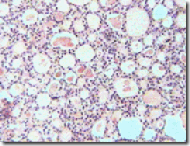

5).-clip_image008

¿Qué ven?

Glándulas ¿qué llaman la atención de esas glándulas?

Los folículos no son redondeados y son de diferente forma y tamaño con más de una capa celular .

Adenocarcinoma

No se puede diferenciar que órgano es.